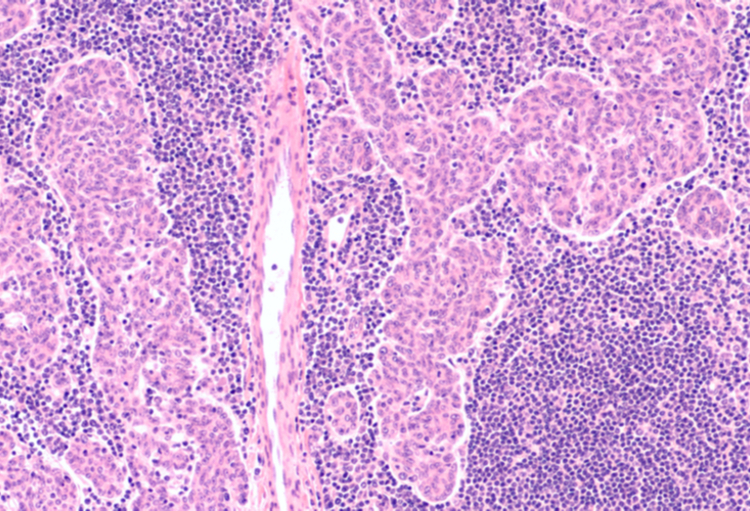

L’incidence des tumeurs thymiques augmente d’année en année, probablement liée partiellement à l’augmentation du dépistage par scanner des cancers du poumon. Cela dit, aujourd’hui, la plupart des patients qui présentent une tumeur thymique sont éligibles à une résection...